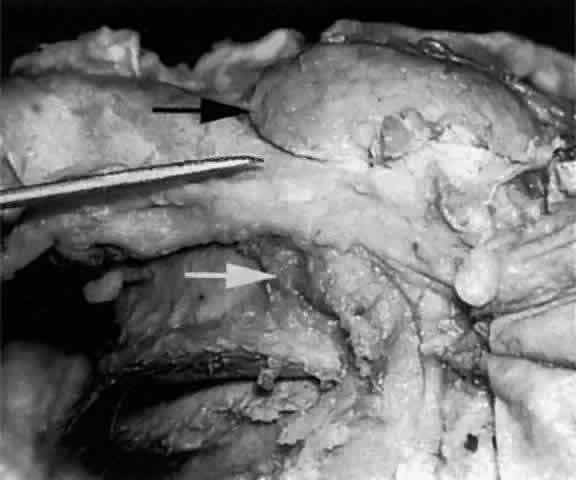

The main lacrimal gland resides in the superotemporal orbit, partially within a shallow bony fossa in the lateral angular process of the frontal bone (fossa glandula lacrimalis). The gland is situated between the eyeball below and the curved orbital wall above, giving it a somewhat compressed and curved shape. It may extend inferiorly to the lateral canthal tendon. The lateral horn of the levator aponeurosis crosses the gland anteriorly, separating it into a larger superior or orbital lobe and a smaller inferior or palpebral lobe (Fig. 2). The division is incomplete because the larger orbital lobe is connected to the smaller palpebral lobe posteriorly by a bridge of glandular tissue, draining tubules, and Müller's muscle, which is attached to the underside of the levator muscle and aponeurosis. The lacrimal gland is surrounded by fibrous tissue that is attached superiorly to the periosteum of the frontal bone and inferiorly to the orbital portion of the zygomatic bone.1

Fig. 2. With the roof and lateral wall of the left orbit removed, this cadaver dissection demonstrates the orbital lobe (black arrow) and the palpebral lobe (white arrow) separated by the lateral horn of the levator aponeurosis (pointer).